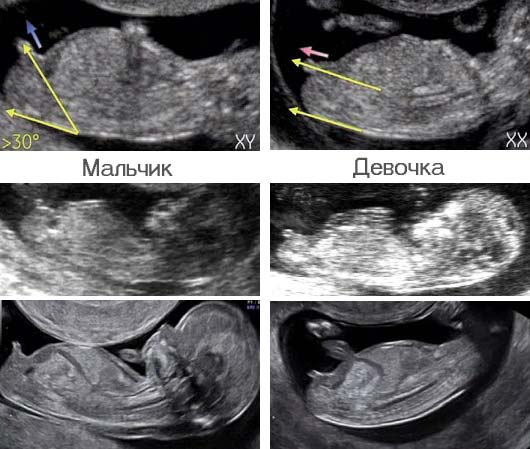

Вот тут прям очевидно, у нас был бугорок уже на этом сроке, на фото автора его не видно, он параллельно.

Девочка Бугорок не торчит, а параллельно спинке

По бугорку девочки смотрят. Это, интересно, 100%? Муж малтчика хочет, про девочку даже не разрешает говорить🤦‍♀️